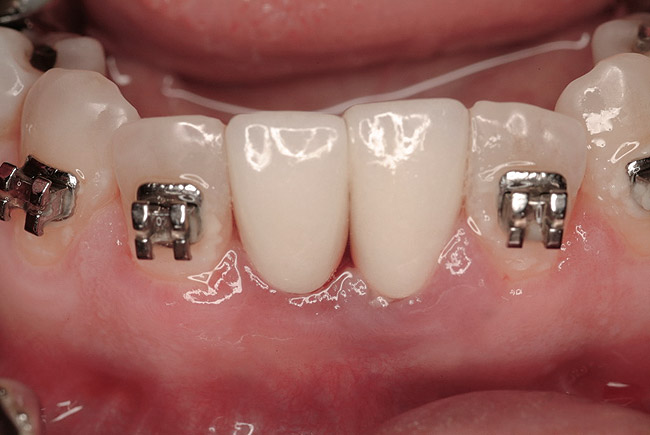

Figure 11  Six months after extraction and augmentation, orthodontic therapy was completed and the patient returned for implant placement. Adequate hard and soft tissues were present.

Figure 11

Figure 12  Flapless, computer-guided implant placement was performed. A transmucosal healing mode was chosen, with the placement of standard healing abutments.

Figure 12